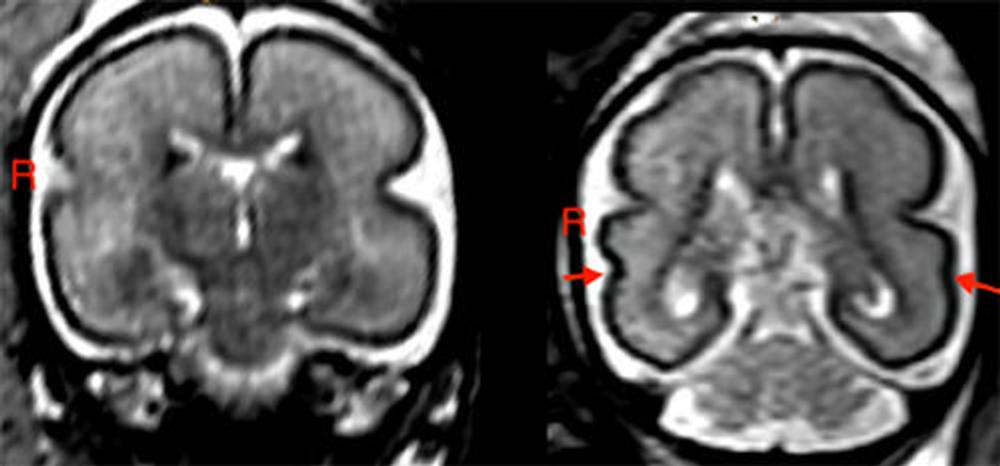

In fetuses with alcohol exposure, the fetal total maturation score (fTMS) was significantly lower than in the age-matched controls, and the right superior temporal sulcus (STS) was shallower. The STS is involved in social cognition, audiovisual integration and language perception.

"We found the greatest changes in the temporal brain region and STS," Dr. Kasprian said. "We know that this region, and specifically the formation of the STS, has a great influence on language development during childhood."

According to the researchers, delayed fetal brain development could be specifically related to a delayed stage of myelination and less distinct gyrification in the frontal and occipital lobes.

Gyrification refers to the formation of the folds of the cerebral cortex. This folding enlarges the surface area of the cortex with limited space in the skull, enabling an increase in cognitive performance. When gyrification is diminished, functionality is reduced.

Figure 1. Left: Fetal brain post-intrauterine alcohol exposure in fetus between 25 and 29 gestational weeks. Note the smooth cortex in frontoparietal and temporal lobes. Right: Brain of matched healthy control case in fetus between 25 and 28 gestational weeks. The superior temporal sulcus is already bilaterally formed (red arrows) and appears deeper on the right hemisphere than on the left.